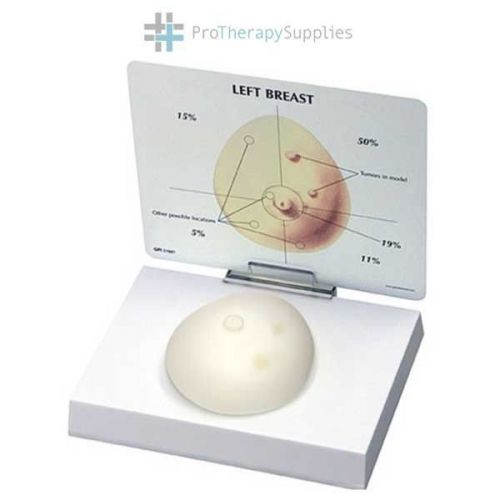

Anatomical Chart Company Breast Cancer Full-size Model